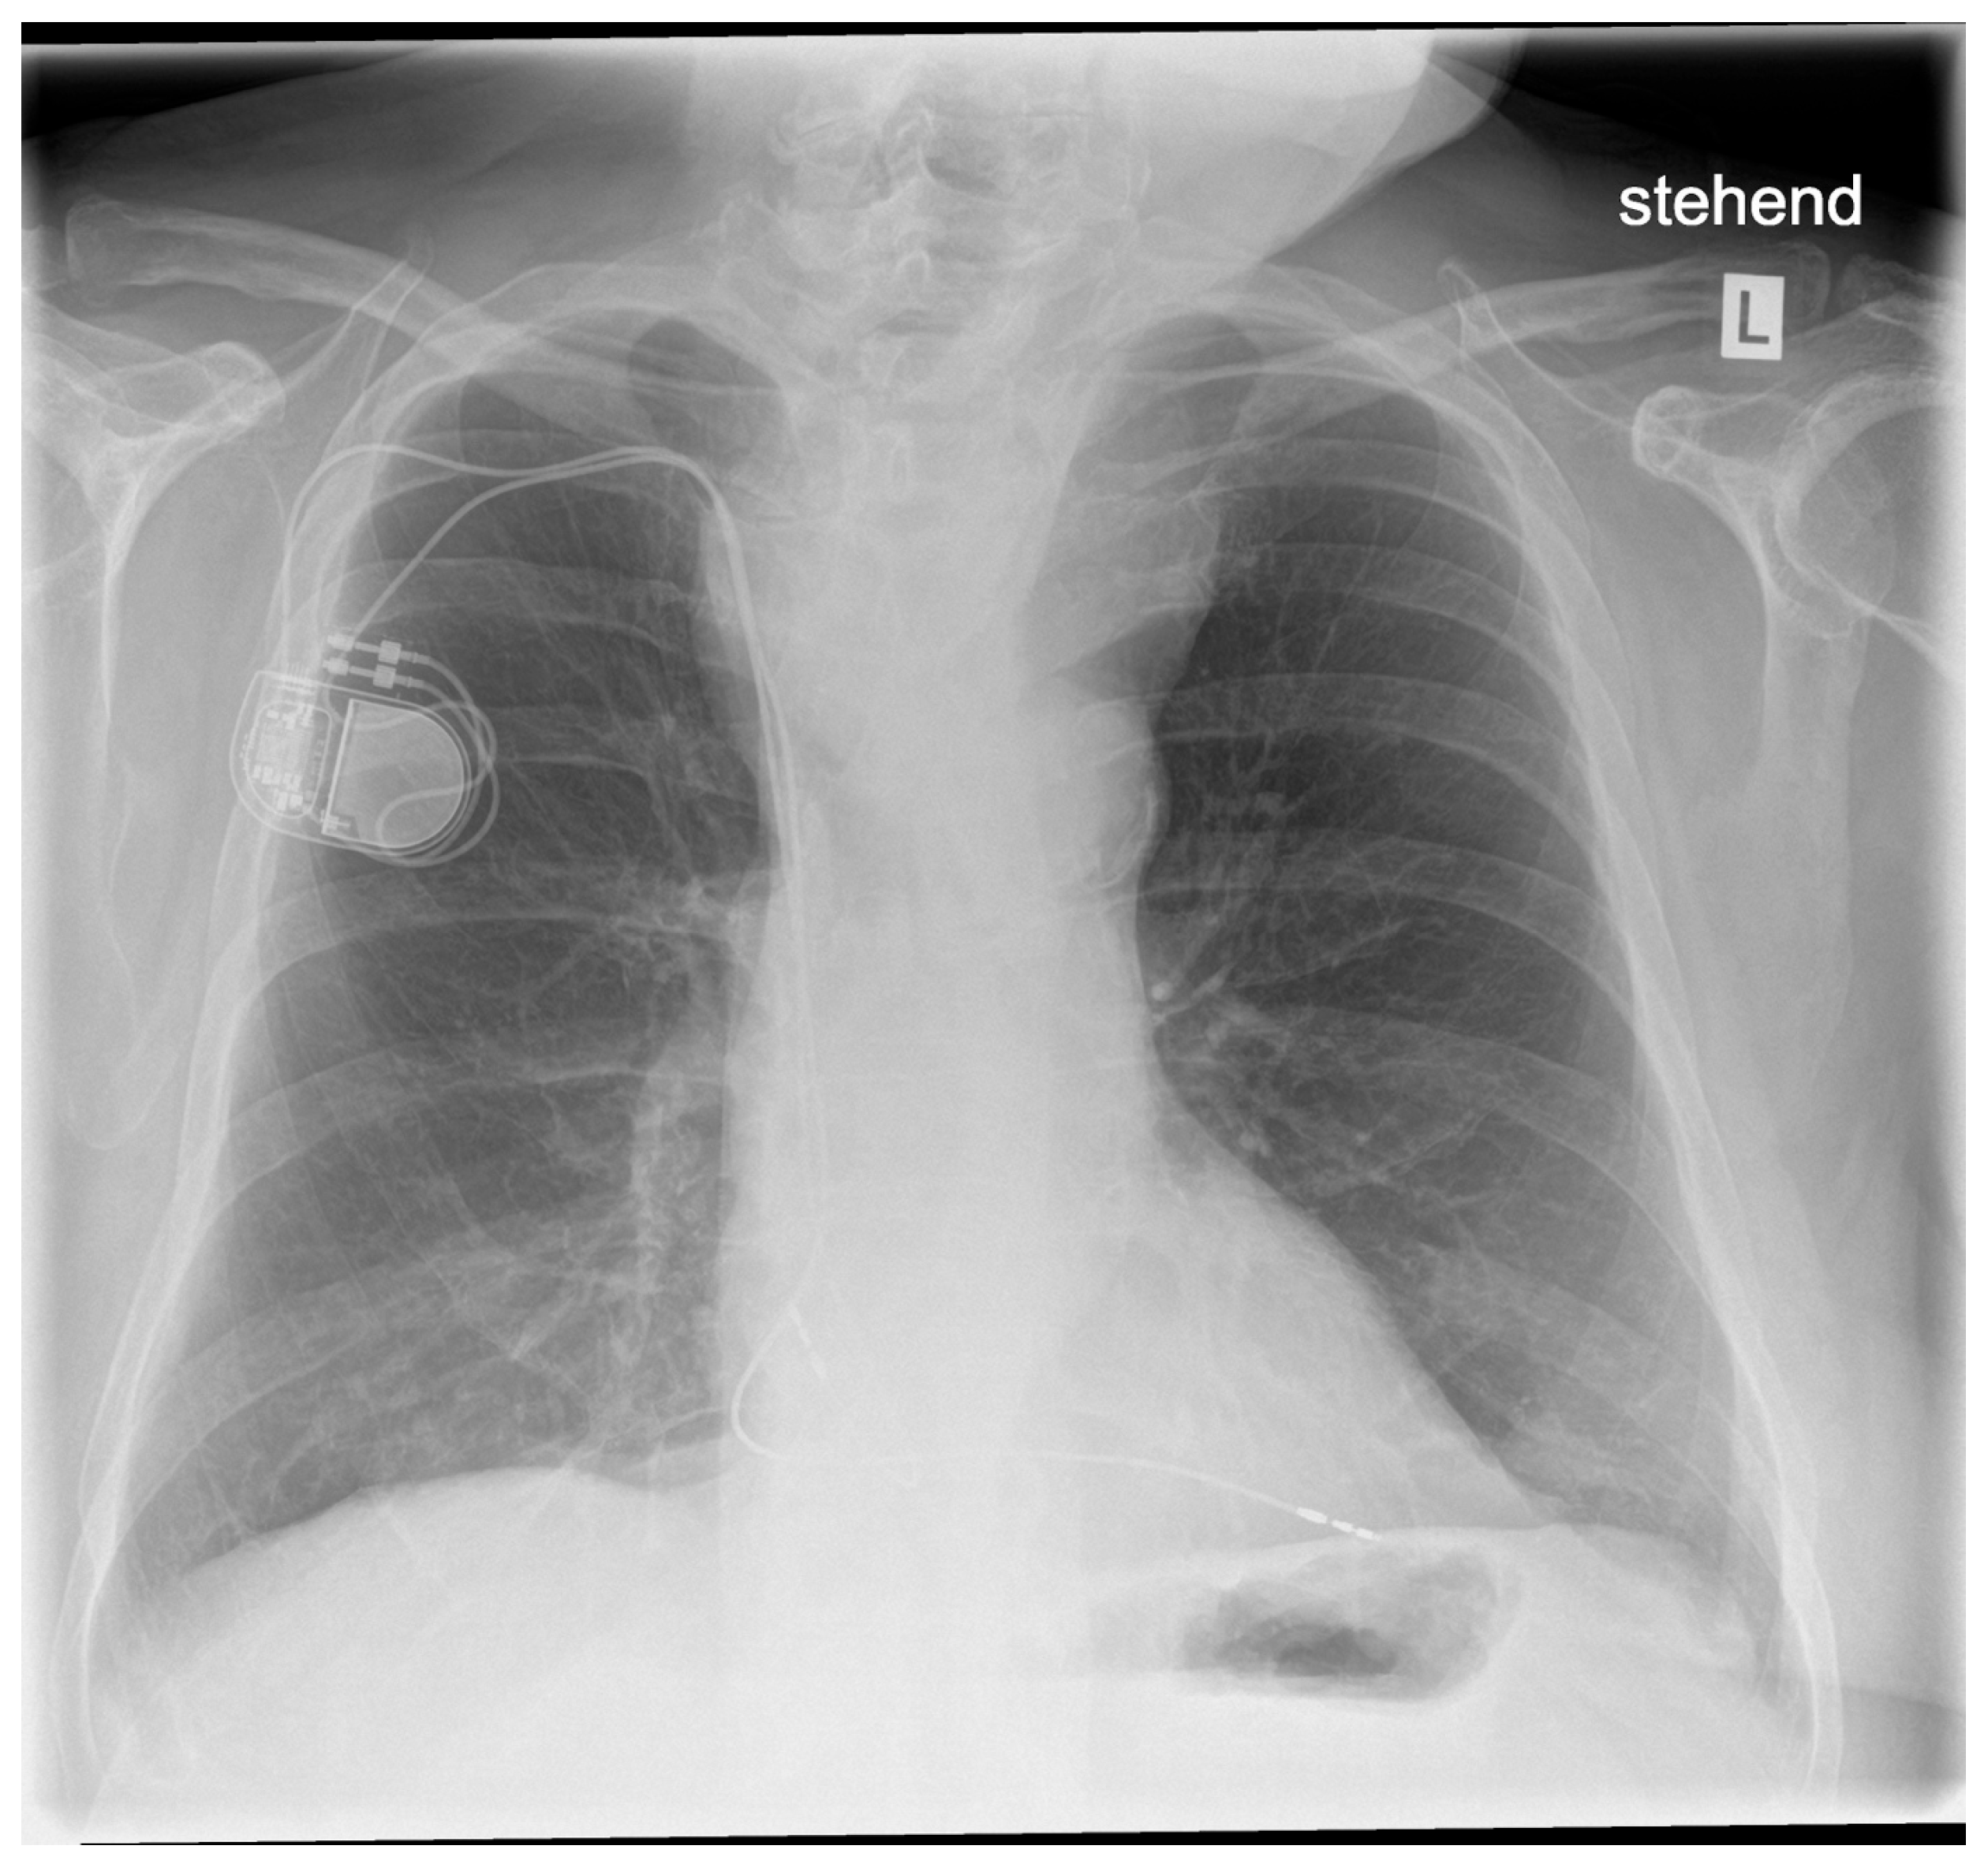

3.1. Risk Classification

3.2. Perioperative Course